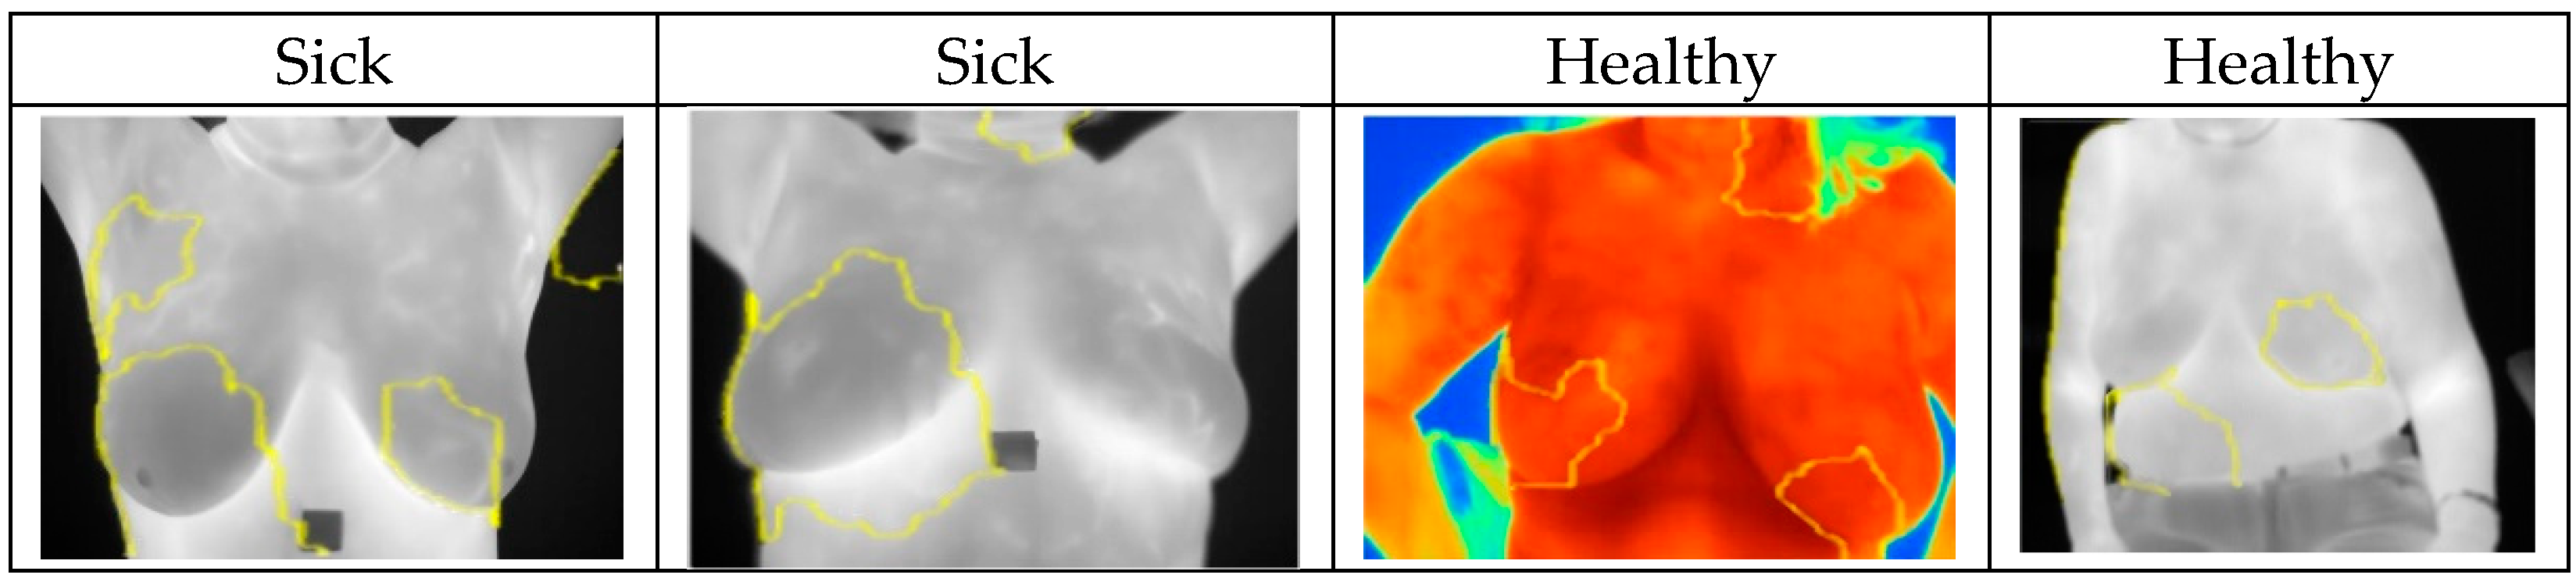

In this case, XAI depicted areas that contributed most when classifying images and assigning them probabilities of being classed “Sick” or “Healthy”. The LIME library that was used to analyze images and the CNN models highlighted areas of thermal images of breast that clearly showed areas indicating movement in the development of cancerous tissues. Explainable parts of images are shown in Figure 11 with their respective diagnoses and classification results.

Figure 11.

Highlighted areas of XAI library images showing parts that contributed to the CNN decision making.